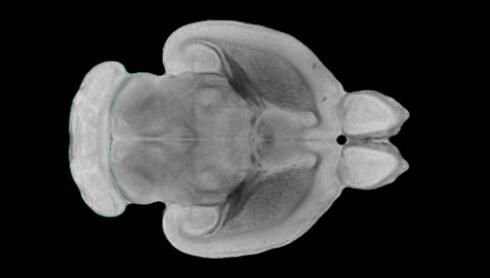

近日,一項刊登在國際雜志Nature上的研究報告中,來自劍橋大學的科學家們通過研究揭示了隨著年齡增長大腦僵硬程度的增加導致大腦干細胞功能異常的分子機制,同時研究者還開發(fā)出了一種新方法能將老化的干細胞逆轉回年齡健康狀態(tài);相關研究結果有望幫助研究人員理解機體大腦的老化過程以及如何開發(fā)治療年齡相關大腦疾病的新型療法。

隨著機體年齡增加,肌肉和關節(jié)都會變得僵硬,這就會使得日常活動變得更加困難,本文研究表明,我們的大腦也是如此,與年齡相關的大腦僵硬對大腦干細胞的功能或許有著重要影響。文章中,研究人員對年輕和老化大鼠的大腦進行研究闡明了年齡相關大腦僵硬對少突膠質(zhì)前體細胞(OPCs,oligodendrocyte progenitor cells)功能的影響。OPCs是一類對維持正常大腦功能非常重要的大腦干細胞,其對于髓磷脂的再生也非常重要,髓磷脂是神經(jīng)組織周圍的脂肪鞘,在多發(fā)性硬化癥中髓磷脂的再生常常會被損傷,機體老化對這些細胞的影響常常會誘發(fā)多發(fā)性硬化癥的發(fā)生,這些細胞的功能在老化的健康人群中同樣會下降。

為了確定老化OPCs的功能缺失是否可以被逆轉,研究人員將來自老化大鼠機體的老化OPCs轉移到了年輕大鼠柔軟的海綿狀大腦組織中去,值得注意的是,這些老化的大腦細胞能夠重新恢復活力,其行為非常像年輕更加強壯的細胞。這項研究中,研究人員在實驗室中開發(fā)出了具有可變僵硬程度的新型材料,并在受控環(huán)境下研究這些材料的生長及其對大鼠大腦干細胞的影響,這些材料能被工程化改造具有和年齡或老化大腦相似的柔軟程度。

為了深入理解大腦組織柔軟和僵硬影響細胞行為的分子機制,研究人員對細胞表面一種名為Piezo1的蛋白質(zhì)進行了分析,該蛋白質(zhì)能“告知”細胞其周圍的環(huán)境為柔軟或僵硬。研究者Kevin Chalut說道,我們發(fā)現(xiàn),當在僵硬材料上促進年輕具有功能性的大鼠干細胞時,這些細胞就會表現(xiàn)出功能異常,并失去其再生的能力,實際上其行為與老化細胞相似。當將老化的大腦細胞在柔軟材料上生長時,其功能就會表現(xiàn)得像年輕細胞一樣,換句話說,其能夠重新恢復年輕的活力。

當研究者從老化大腦干細胞的表面剔除Piezo1蛋白后,他們就能夠誘騙細胞感知柔軟的周圍環(huán)境,甚至當將細胞在僵硬材料上生長時也是如此。此外,當在老化大鼠大腦中剔除OPCs上的Piezo1時,就會促進細胞變得年輕并再次承擔正常的再生功能。研究者Susan Kohlhaas表示,多發(fā)性硬化癥是一種痛苦讓患者致殘的疾病,隨著時間推移,我們迫切需要開發(fā)出減緩并抑制患者殘疾的新型療法。這項研究中,研究人員闡明了大腦干細胞老化的分子機制,以及如何通過逆轉該過程來實現(xiàn)恢復大腦干細胞活力,后期研究人員將會基于本文研究開發(fā)出新型療法來治療多種與老化和多發(fā)性硬化癥相關的疾病,包括如何潛在恢復大腦失去的功能等。